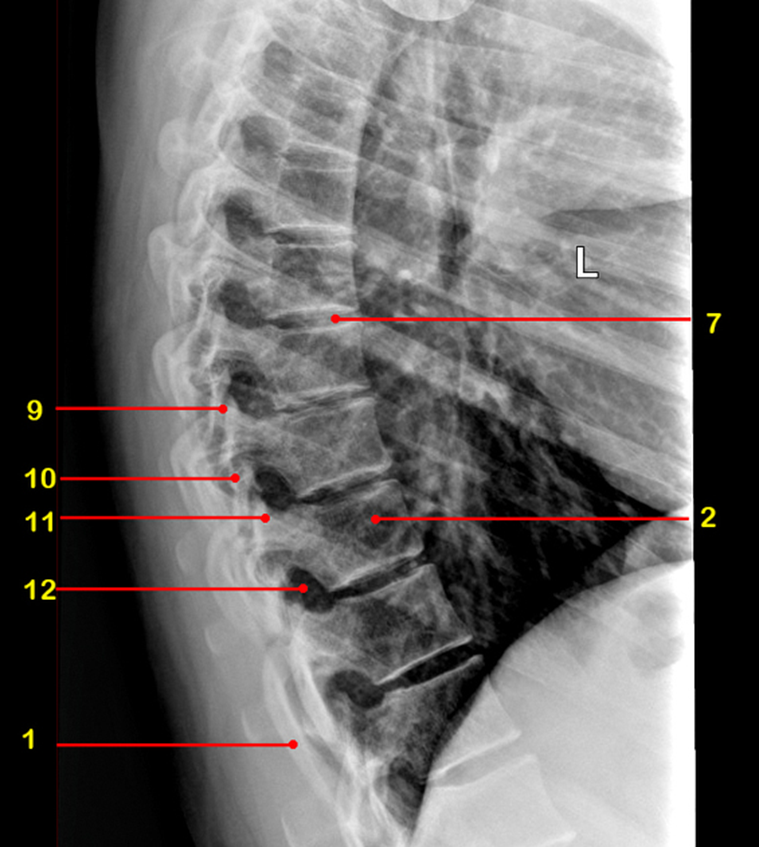

What is 9

facet joint

What is 10

inferior articular process

What is 11

superior articular process

What is 12

intervertebral foramen

What view is this

sagittal